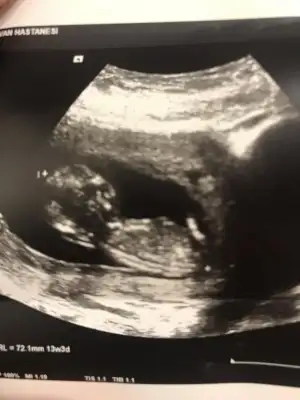

Sizce benimkinin cinsiyet nedir

Merhaba😊 dün kendimi çok yordum akşam birden su geldi oldukça fazla. Bugün de devam edince doktora gideyim dedim ilk haftalarda çok kanamam olduğu için hala devam ediyorum progestana. İnternette araştırınca amniyon sıvısı gelmiş olabilir diye düşündüm 😕 neyseki bu haftalarda olmazmış enfeksiyon belirtisiymiş. Bebişin suyu iyi 😊 ama cinsiyet tahmini yapmadı sizce belli mi

Eklentiler

• A933AECB-E3DD-4EAD-B534-0423191D0F80.webp

A933AECB-E3DD-4EAD-B534-0423191D0F80.webp

21,9 KB · Görüntüleme: 114